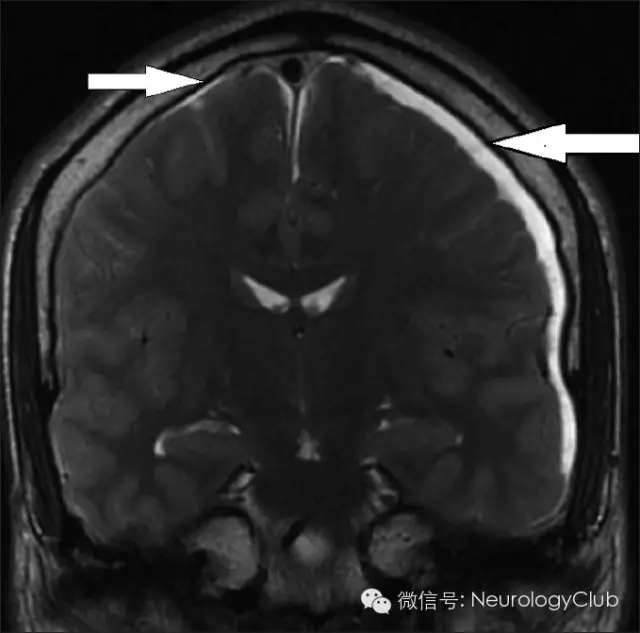

(1)硬膜下积液(Subdural fluid collections)

硬膜下积液表现为双侧对称性薄层积液,无占位效应,对下面的脑沟脑裂无压迫效应。